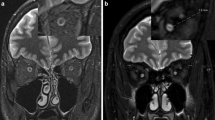

DTI was preprocessed for denoising and corrected for eddy current and motion artifacts using MRtrix3 software (http://www.mrtrix.org) based on published methods15,16,17,18,19. The susceptibility-induced off-resonance field and subject head motion was estimated using two pairs of b0 images with distortions in opposite directions. One corrected b0 image was generated, and then this estimated field was applied to correct the entire diffusion data. This method is based on registering the individual volumes of the diffusion data set to a model-free prediction to account for unique eddy current distortions present in each volume and any subject movement between the acquisition of successive volumes20. Subsequent processing was performed using the mrDiffusion implemented in Vistasoft (https://github.com/vistalab/vistasoft). The corrected diffusion data, as a set of 49 images, were co-registered to the anterior commissure—posterior commissure aligned T1 image using a rigid-body mutual information algorithm. Diffusion-weighting gradient directions were reoriented by applying the same transformation used on the diffusion-weighted images and resampled to 2 mm isotropic voxels using trilinear interpolation. Finally, the tensors were estimated to compute FA, MD, RD, and AD using a least-squares algorithm with bootstrapping for 500 times21. Overview of the DTI analysis and details of diffusion measures for ONs are illustrated in Fig. 1. Plotting tensor model and fiber tract on MRI was done using FSLeyes (v0.34.2) https://fsl.fmrib.ox.ac.uk/fsl/fslwiki/FSLeyes) and Matlab Brain Anatomy (MBA, https://github.com/francopestilli/mba). The main diffusion properties for FA and RD in our analysis are visualized in Fig. 2B.

Overview of diffusion tensor imaging (DWI) analysis. (A) Preprocessing of raw DWI data. A set of 50 images was acquired from each participant, including 48 sampling directions and two b0 images of anteroposterior (AP) and posteroanterior (PA) phase-encoding directions (i). One corrected b0 image was generated, and the entire diffusion data was applied by estimating artifacts from two pairs of b0 images (ii). Finally, a set of 49 images was co-registered to the T1 image (iii). (B) Diffusion tensor model. To represent the optic nerve in the axial (i), sagittal (ii), and coronal (iii) views on the FA image, diffusion directionality was color-coded with green representing anterior–posterior directions, red representing left–right directions, and blue representing superior-inferior directions for a single subject using FSL eyes. A close-up view of 3 × 3 voxels of the optic nerve behind the eye globe in the axial (iv), three voxels in the sagittal (v), and three voxels in the coronal views (vi). The diffusion tensor D was estimated from a set of DWIs. The three orthotropic axes of a diffusion ellipsoid can be determined by the decomposition of the tensor into eigenvectors and eigenvalues (vii). (C) Tensor-derived diffusion measures. Cropped image of the fractional anisotropy (FA) (i), mean diffusivity (MD) (ii), axial diffusivity (AD) (iii), and radial diffusivity (RD) (iv). FA values are bounded between zero (a perfect sphere) and one (an infinitely long cigar shape). MD is the mean of the eigenvalues of the diffusion tensor. AD indicates an eigenvalue of λ1, which is diffusivity along the principal axes, while RD is diffusivity along non-principal axes by averaging the eigenvalues of λ2 and λ3. (D) Optic nerve fiber tractography. Two spherical regions of interest (ROIs) are placed posterior to the globe of the eye and in the orbital apex at the center of the annulus of Zinn to identify the optic nerve pathway. Placement of the two ROIs overlaid on T1 (i) and FA image (ii). Visualization for cleaned optic nerve tractography (iii) and a central fiber in the optic nerve passing through the ROI (iv).

Visualization of the average peripapillary retinal nerve fiber layer (RNFL) thickness, diffusion measures, and tract profiles of six patients with optic nerve atrophy. (A) A plot indicating the average temporal-superior-nasal-inferior-temporal RNFL thickness of optic nerve head, measured at a circle with a diameter of 3.4 mm centered on the disc by optical coherence tomography. The RNFL thickness of the atrophic eyes (solid line) was significantly reduced compared to that of contralateral non-affected eyes (dashed line). (B) Optic nerve pathway mapping by the average fractional anisotropy and radial diffusivity (\(\upmu\)m2/s) values for six atrophic optic nerves (ONs) and six non-affected ONs are presented in the left and right, respectively. (C) Average tract profiles across the ONs of six atrophic (red) eyes and six non-affected (gray) eyes plotted by mean lines with standard deviation and each node marked with dotted lines. Five nodes nearest the optic nerve head were excluded from the analysis and are shaded white in the graph.

Group differences in diffusion measures of the ONs are shown in Fig. 3. FA of atrophic ON was significantly lower than that of non-affected and control ONs (atrophic [A], 0.136 ± 0.059; non-affected [N], 0.384 ± 0.048; control [C], 0.389 ± 0.053; A vs N, P < 0.001; A vs C, P < 0.001). Also, MD and RD of atrophic ONs were significantly higher than those of non-affected and control ONs (MD, A, 0.988 ± 0.247; N, 0.658 ± 0.058; C, 0.687 ± 0.079; A vs N, P = 0.010; A vs C, P = 0.002; RD, A, 0.920 ± 0.247; N, 0.510 ± 0.054; C, 0.532 ± 0.078; A vs N, P = 0.003; A vs C, P < 0.001). AD did not show significant differences between the groups (A, 1.123 ± 0.252; N, 0.955 ± 0.080; C, 0.998 ± 0.094; A vs N, P = 0.152; A vs C, P = 0.155). Figure 2B,C visualizes the significance differences in average FA and RD between atrophic and non-affected ONs. Figure 2C shows the average tract profiles across the ONs.